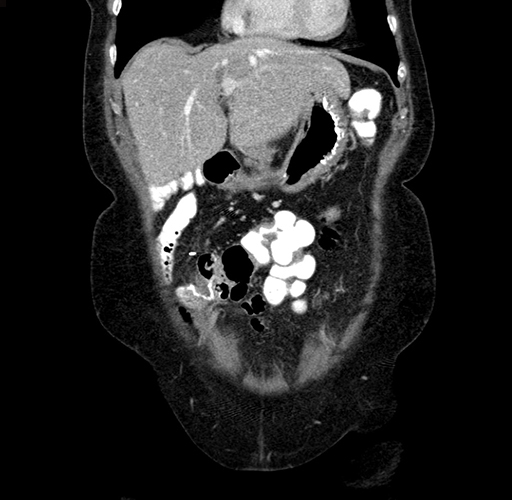

Pre-Chemo: Coronal Venous

Coronal Venous